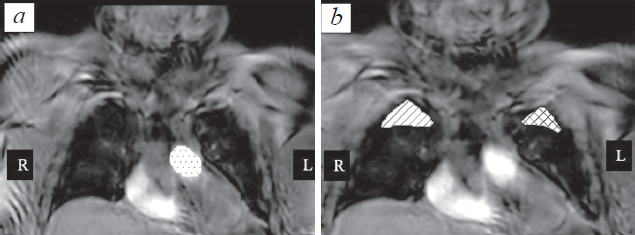

Materials and methods. 10 volunteers with no signs of interstitial lung disease were examined by three-dimensional ultrafast dynamic contrast-enhanced MR imaging using 3D T1-weighted images. The values of pulmonary blood flow (PBF), mean transit time (MTT), and pulmonary blood volume (PBV) for the targeted regions of interest were calculated based on the dynamic image series. For calculations, arterial input function (AIF) was used, as well as the time-intensity curves.